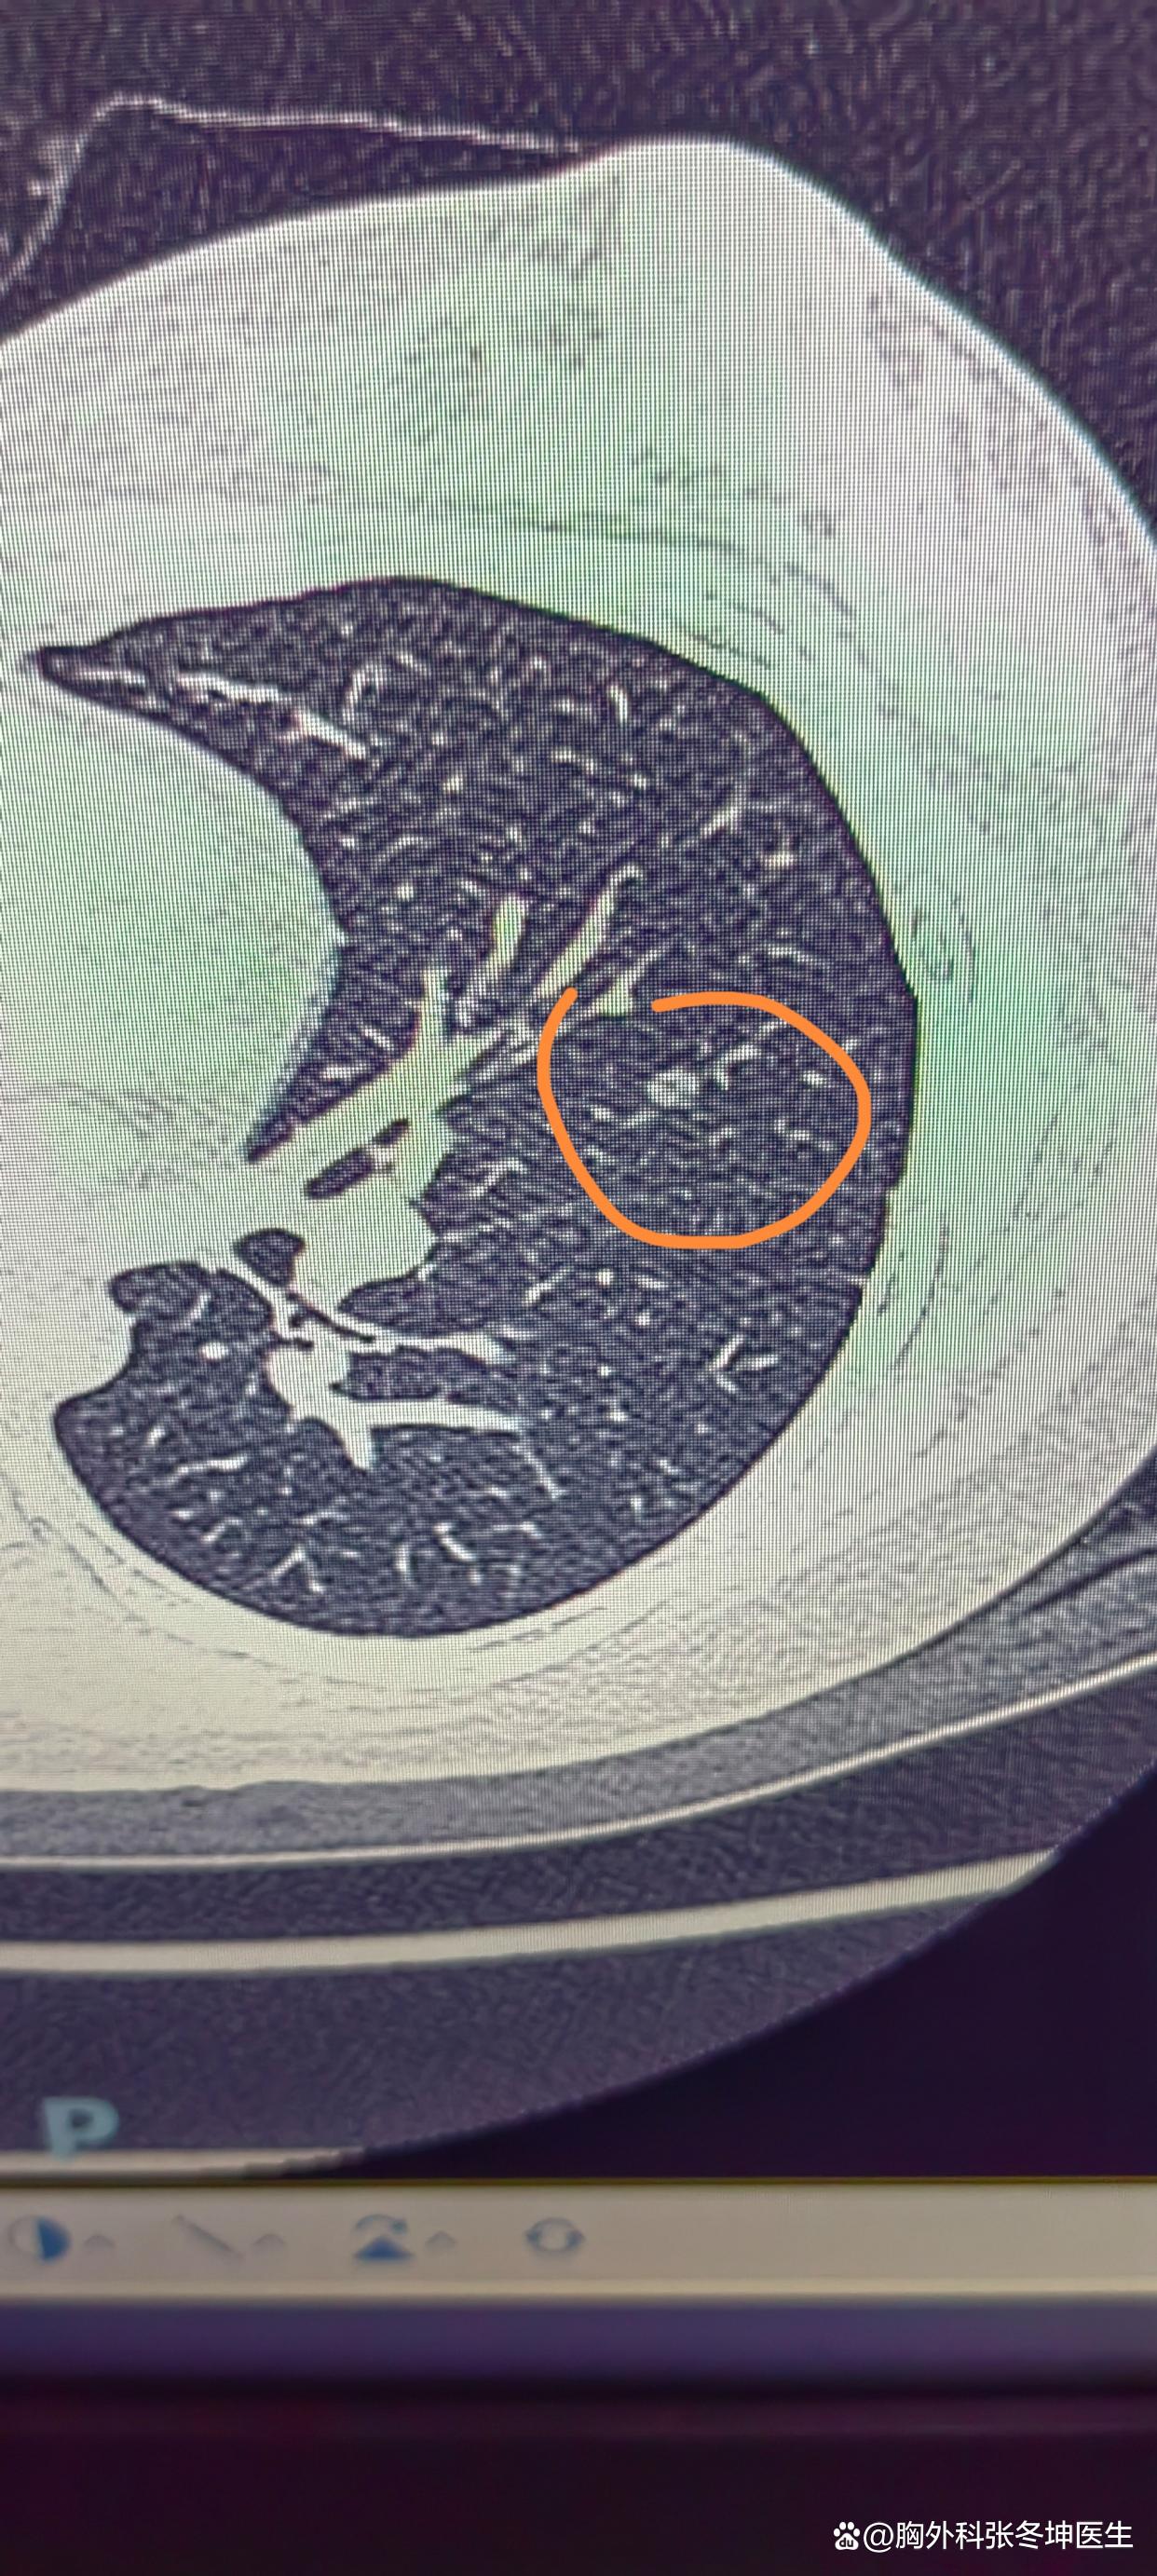

肺部磨玻璃结节会消失吗

1、磨玻璃肺结节是否会自动消失,取决于其成因1 由炎症引起的磨玻璃肺结节可能会自动消失 部分磨玻璃结节是由急性支气管炎哮喘慢阻肺等炎症性疾病引起的当这些炎症得到控制或治愈后,由炎症引起的磨玻璃肺结节有可能会自动消失特...